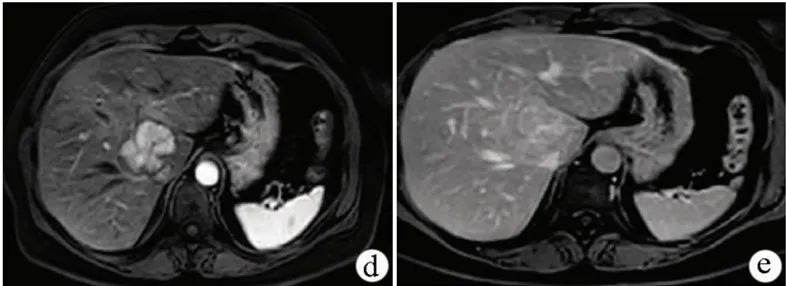

图3 腹部CT造影(白色箭头)和MRI T2加权扫描(黄色箭头)